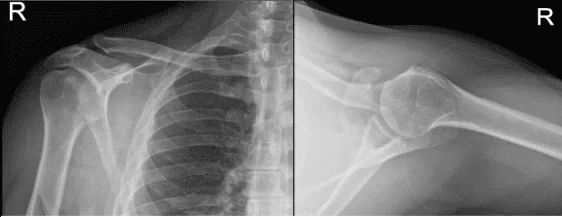

Se presentaron radiografías del hombro derecho e izquierdo. En el hombro derecho no hubo fracturas agudas, aunque hay un ensanchamiento asimétrico de la articulación acromioclavicular del hombro derecho y, para una evaluación adicional, se recomienda correlacionarse con la resonancia magnética. Por otro lado, la radiografía del hombro izquierdo mostró radiografías normales.

Radiografía del hombro derecho

Radiografía del hombro izquierdo